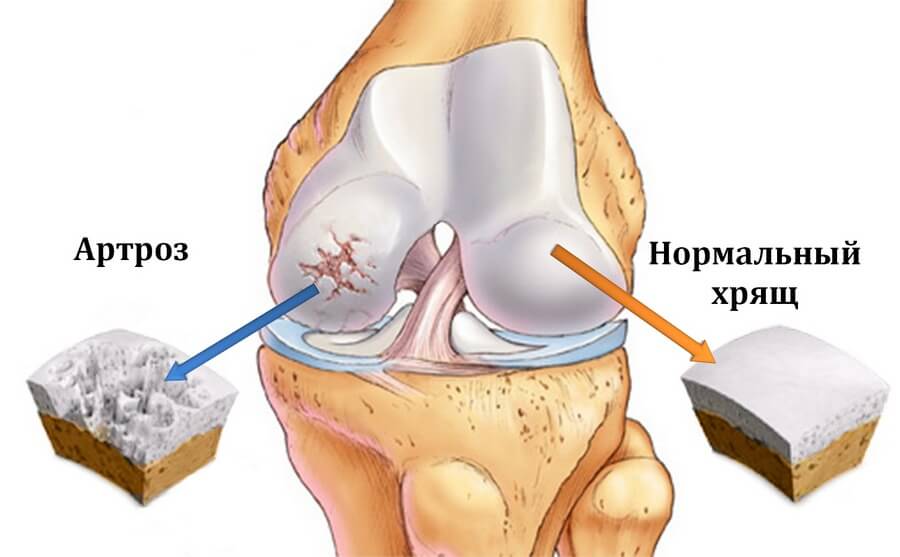

Это хроническое заболевание, которое не имеет воспалительной природы, вызвано поражением суставов и его составных частей. Возникает оно в основном у людей старшей возрастной группы – кому исполнилось более 50 лет, но и молодые люди тоже входят в эту группу риска, хотя гораздо реже.

- сужается суставная щель;

- происходят утолщения и уплотнения суставной капсулы;

- утолщается хрящевой слой;

- в суставе начинает собираться жидкость, и именно она сковывает подвижность;

- разрастаются кости – неофиты, но такая патология происходит только в том случае, если болезнь не лечится.

Полиостеоартроз – это хроническое заболевание, характеризующееся дегенеративными изменениями в суставах, которое затрагивает несколько суставов одновременно. Он приводит к разрушению хрящевой ткани, изменению формы суставов и ограничению их подвижности, что может вызывать боль и дискомфорт при движении.